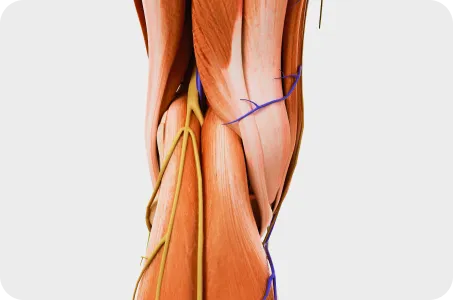

근육과 근막의 정렬을 함께 진단하며, 풀 스파인 촬영을 통해 머리부터 모든 고관절, 발의 정렬까지 함께 파악하여 개개인에 맞는 전신 치료법을 설계합니다.

모아레 근육 균형 검사

Skin rolling 근막 검사

교정 기간이 개인마다 다른 이유 중 하나는 근육량과 근육 상태에 따른 차이입니다. 근육은 뼈와 관절을 지지하며 체형을 유지하는 중요한 역할을 합니다. 하지만 개개인의 근육량과 근육의 균형 상태는 다르기 때문에 교정 효과가 나타나는 속도에도 차이가 생깁니다. 근육량이 충분하고 근력이 균형을 이루고 있는 경우, 교정된 체형이 안정적으로 유지되기 쉽지만 근육량이 부족하거나 특정 부위의 근육 불균형이 심하다면 교정된 체형이 쉽게 틀어질 수 있어 더 오랜 치료와 강화 운동이 필요합니다.